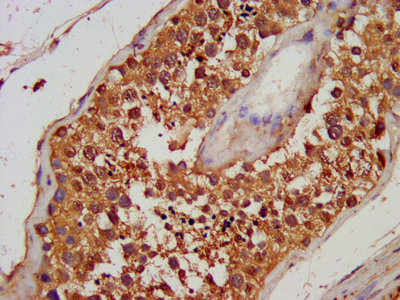

IHC image of CSB-PA12325A0Rb diluted at 1:100 and staining in paraffin-embedded human testis tissue performed on a Leica BondTM system. After dewaxing and hydration, antigen retrieval was mediated by high pressure in a citrate buffer (pH 6.0). Section was blocked with 10% normal goat serum 30min at RT. Then primary antibody (1% BSA) was incubated at 4°C overnight. The primary is detected by a biotinylated secondary antibody and visualized using an HRP conjugated SP system.